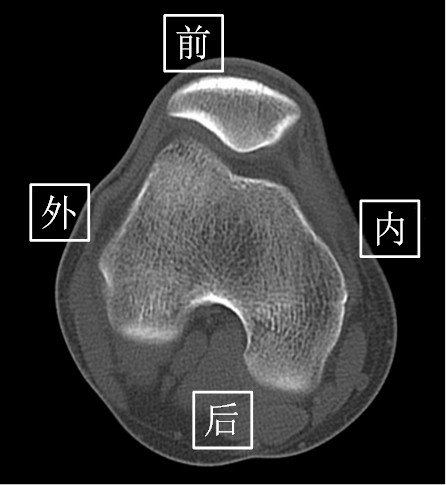

2.CT(以膝关节为例)

由于CT 是三维成像,包括矢状面,冠状面和横断面三个层面的扫描。一张CT片子也是包括医院、姓名、性别、年龄、检查日期、侧别、扫描序列等信息的。

矢状面---是从前向后、从内往外扫描成像。

冠状面---是从内向外、从前往后扫描成像。

横断面---是从上向下、从前往后扫描成像。